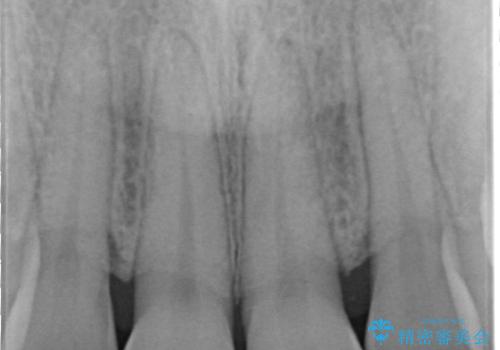

前歯の形気になる セラミッククラウン(SP)

- 矯正終了した患者様で、前歯の形が気になるということで

セラミッククラウンにて治療された方の症例です。

また、神経がある歯なのでシミたりすることが場合によってはありますので、担当歯科医師にご相談ください。